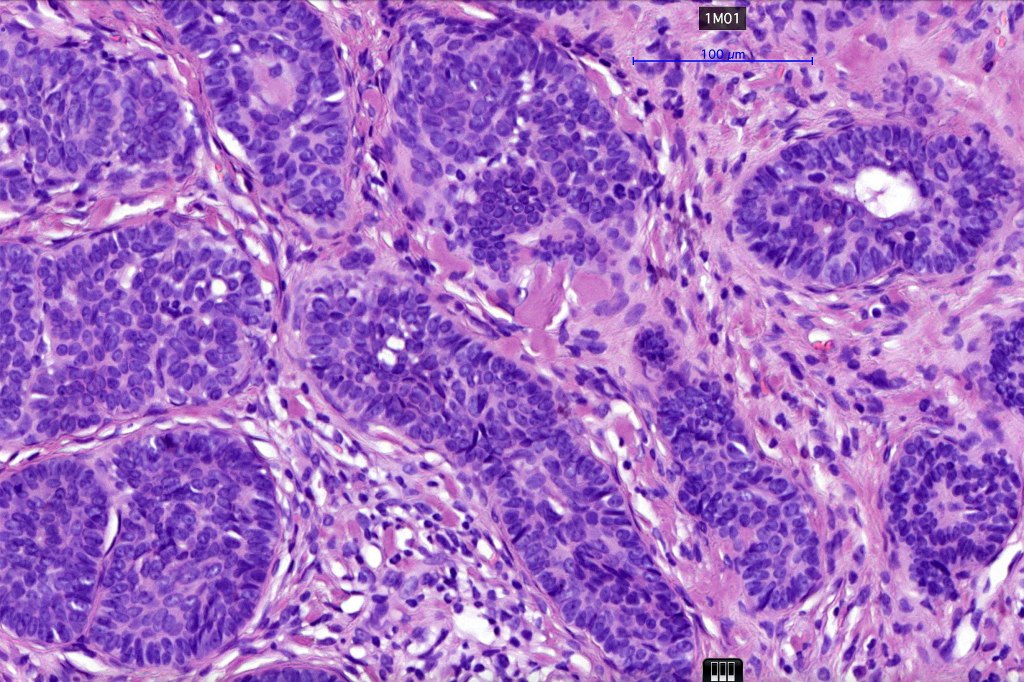

•Basaloid lobules show peripheral palisading

•Retraction artifact and mucin deposition as seen in BCC are not present

•Perifollicular mesenchyme is always conspicuous and sometimes densely aggregated are seen indenting the baslaloid lobules (papillary mesenchymal bodies)

•Narrow epithelial strands arising from the basaloid lobules are often present

Trichoepithelioma should be distinguished from trichoblastoma since the latter is very rarely syndromic. Trichoepithelioma is largely a dermal tumor whereas trichoblastoma often extends from the dermis into subcutaneous fat or deeper in very large examples. Papillary mesenchymal bodies are much better formed and generally more obvious in trichoepithelioma. Trichoepithelioma must also be distinguished from basal cell carcinoma. Retraction artifact & stromal mucin are features of basal cell carcinoma and not trichoepithelioma. Papillary mesenchymal bodies are not seen in basal cell carcinoma.